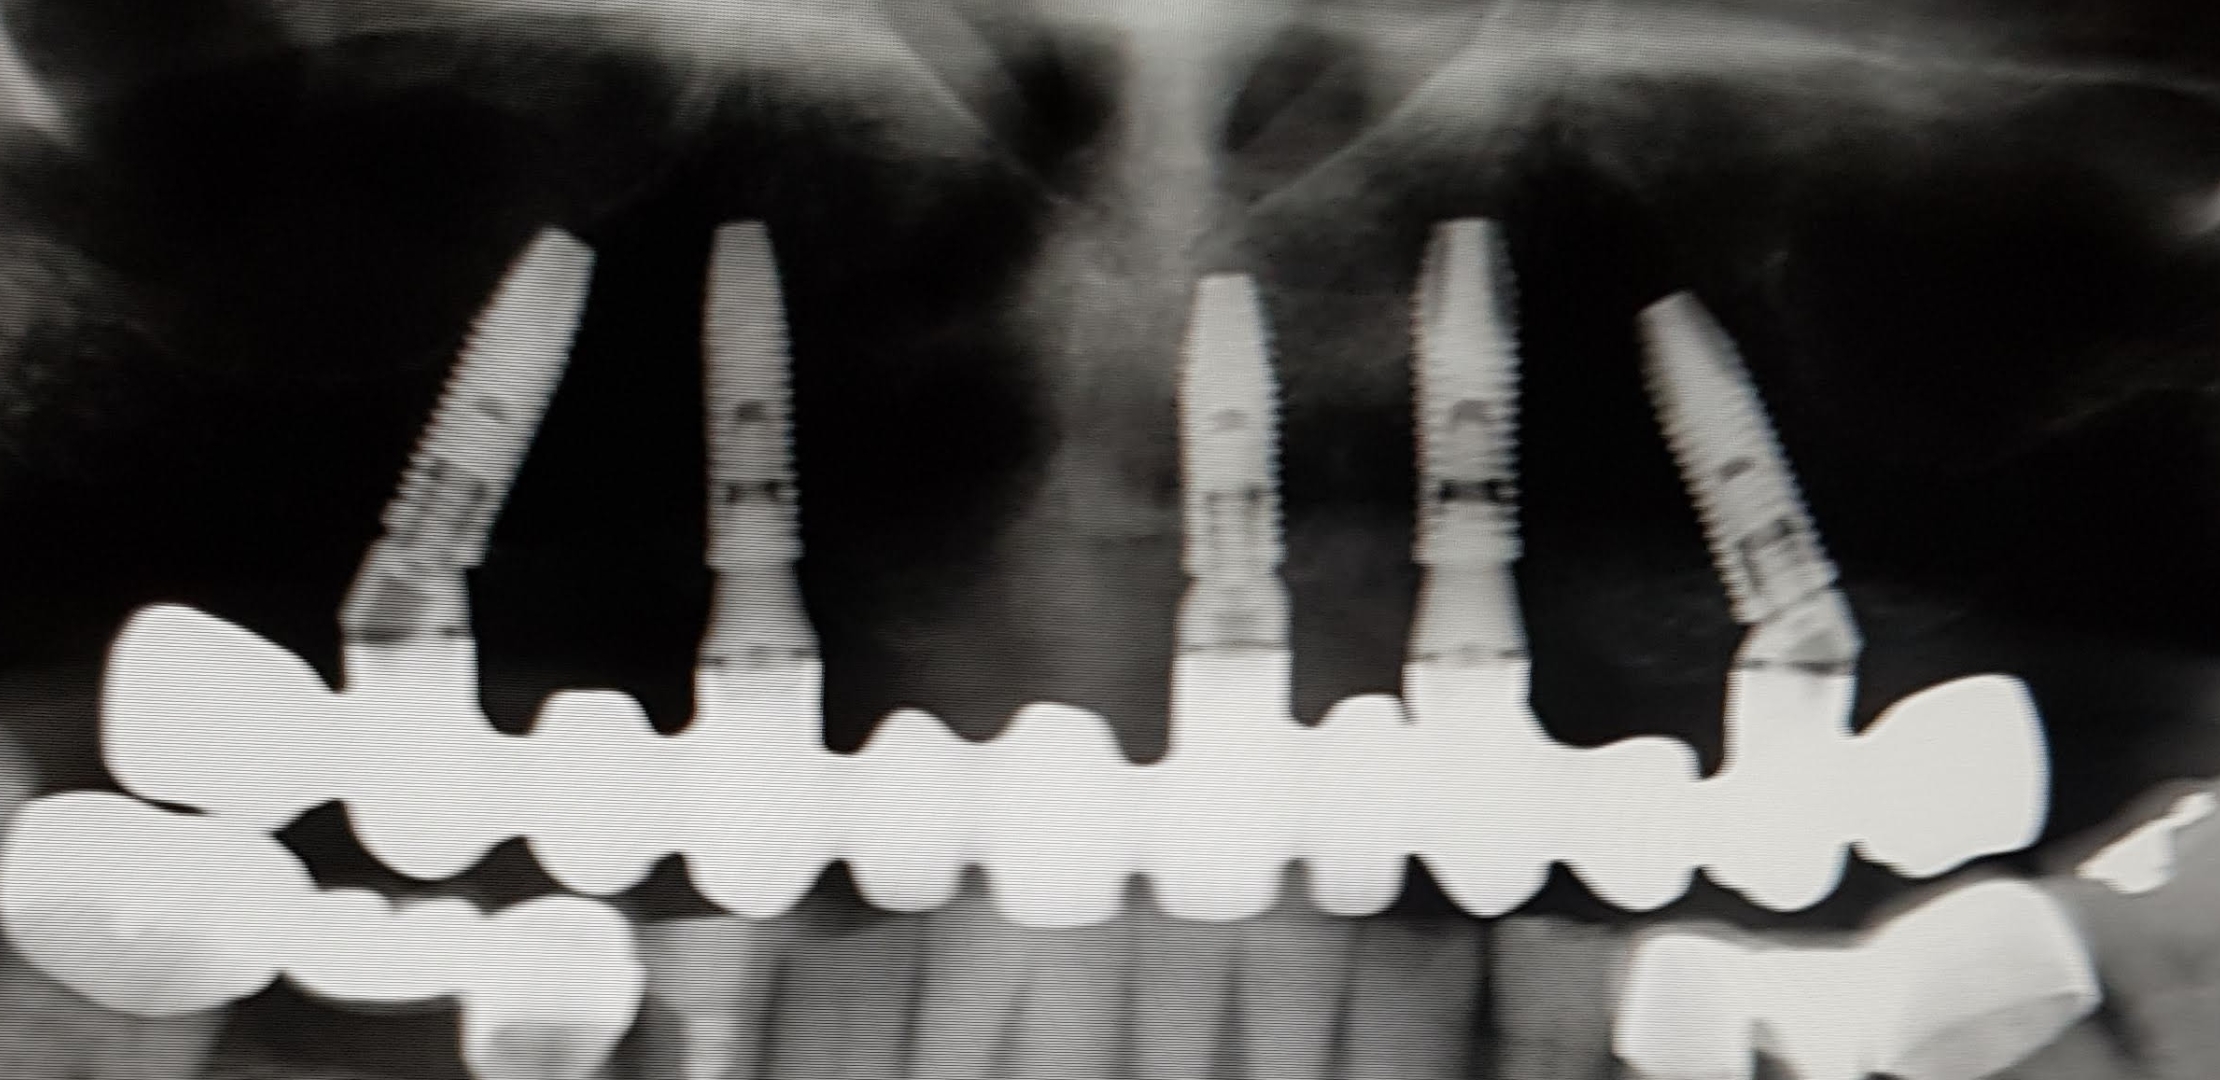

Felső fogatlan állcsont korszerű ellátása: felső teljes fogatlanság kezelése 5 implantátumon rögzített fix híddal, szabadvégekkel. Multi unit tengelykorrekciós fejek, csavarosan rögzített híd.

Implantátum: Nobel Biocare.

Hídpótlás anyaga: lézer szinter fémvázra égetett porcelán.

A választott fogszín: A1.

A protetikai munka elkészülésének ideje: 8 munkanap.